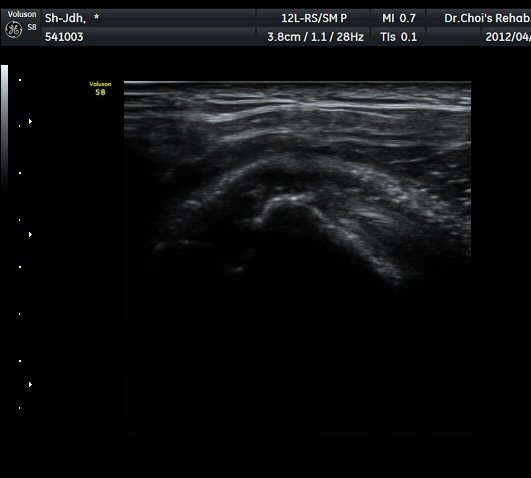

¾î±ú µÚ °üÀý¼ø °Ë»ç¿¡¼­ °üÀý¼ø Ç¥Ãþ¿¡ Àú¿¡ÄÚ ¼ö¾×Àú·ù°¡ °üÂûµÊ(»çÁø 4).

ŽÃËÀÚ¸¦ Á» ´õ µÚ·Î À̵¿ÇÏÀÚ °üÀý¼ø ³»Ãø °¡½Ã°üÀý¿À¸ñÆÐÀÓ(spinoglenoid notch)¿¡

¿øÇü¸ð¾çÀÇ Àú¿¡ÄÚ ³¶Á¾ÀÌ °üÂûµÊ(»çÁø 5, 6).